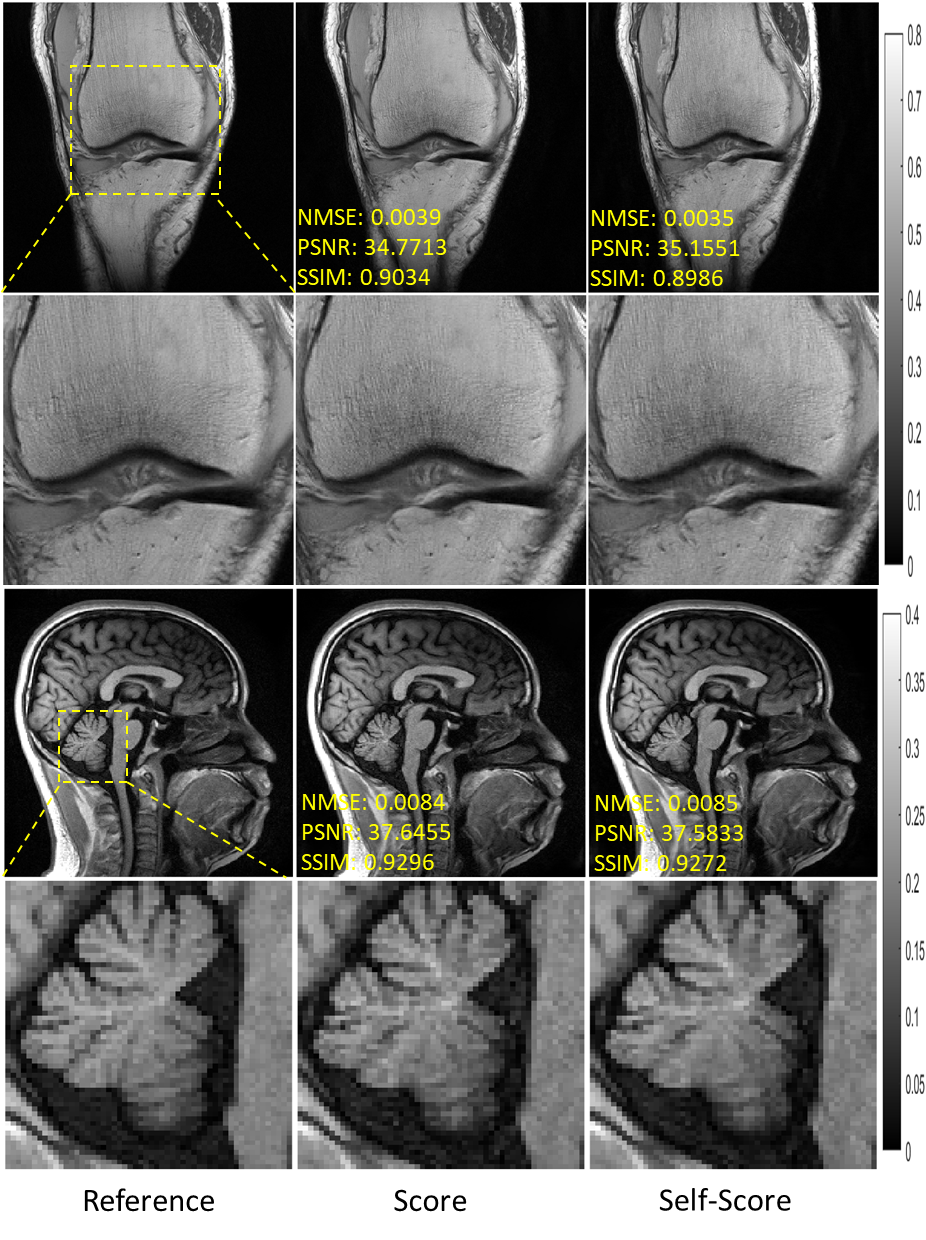

Figure 7 shows the reconstruction results of the conventional score-based method (termed score) and our proposed self-supervised score-based method (termed self-score) for fastMRI knee and SIAT brain data under 6-fold and 4-fold uniform undersampling, respectively. In terms of visual perception, the two methods perform almost identically. The quantitative metrics are shown in Table 4. It can be found that the proposed self-score method performs almost identically to the score method on the fastMRI knee dataset and even slightly better than the score on the SIAT brain dataset. This experiment validates the accuracy of the proposed self-supervised learning method for data distribution estimation.

Refer to caption

Figure 7: Reconstruction of the fastMRI knee (first two rows) and SIAT brain (last two rows) data at uniform undersampling of R=6𝑅6R=6 and R=4𝑅4R=4, respectively. The values in the corner are NMSE/PSNR/SSIM values. Second and fourth rows illustrate the enlarged views. The grayscale of the reconstructed images is at the right of the figure.